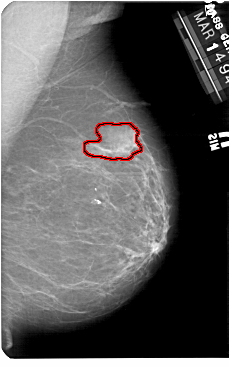

A_1182_1.LEFT_MLO

LEFT_MLO LINES 5491 PIXELS_PER_LINE 3511 BITS_PER_PIXEL 12 RESOLUTION 43.5 NON_OVERLAY

FILE: A_1182_1.RIGHT_MLO.OVERLAY

TOTAL_ABNORMALITIES 1

ABNORMALITY 1

LESION_TYPE MASS SHAPE IRREGULAR MARGINS ILL_DEFINED

ASSESSMENT 4

SUBTLETY 5

PATHOLOGY MALIGNANT

TOTAL_OUTLINES 1

BOUNDARY